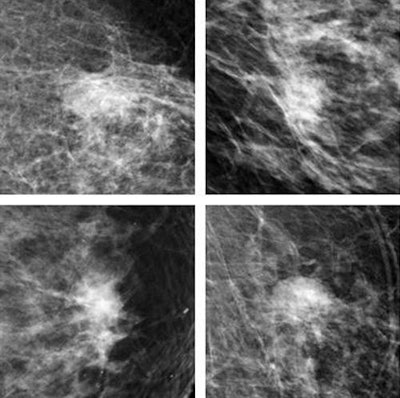

Top row: CNN correctly identifies breast malignancies. Bottom row: Benign findings misidentified by CNN as malignancies tended to be common abnormalities such as cysts that were easy for radiologists to exclude. Recognition of benign abnormalities will be built into future versions of the CNN. All images courtesy of Thijs Kooi."We believe deep learning methods signify a paradigm shift in CAD and expect to see a lot of breakthroughs in the next couple of years," lead author Thijs Kooi, a doctoral candidate in Radboud University's Diagnostic Image Analysis Group, told AuntMinnieEurope.com. "We have shown we can get state-of-the art performance and operate at a level of expert human readers with relatively little engineering effort. Results also show the performance of the CNN increases with more training examples, and we expect it to become even better if more data is available."